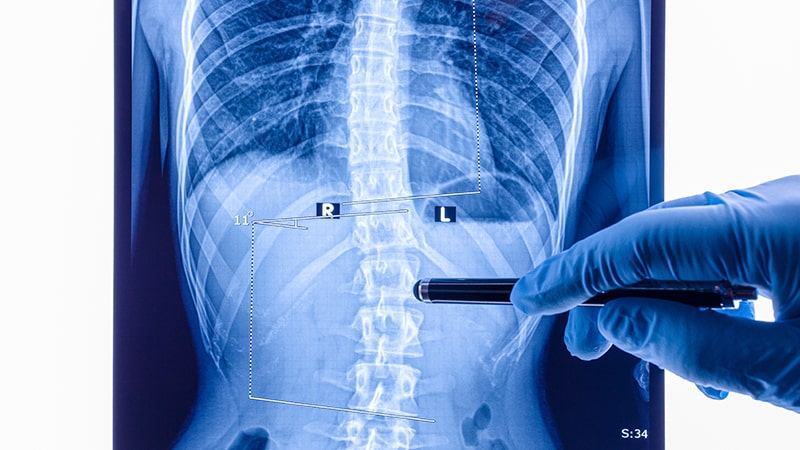

La subluxación vertebral es un concepto teórico en quiropraxia que describe una supuesta disfunción en el movimiento de una vértebra, lo que, según los quiroprácticos, puede causar cambios patológicos en nervios, músculos, ligamentos y tejido conectivo, y se cree que es la causa de diversos trastornos de salud. Se argumenta que estas subluxaciones pueden afectar la función nerviosa y la salud en general.

La subluxación vertebral, si no se trata adecuadamente, puede tener consecuencias a largo plazo en la salud. De hecho, se considera una disfunción del complejo articular vertebral que compromete el equilibrio de las articulaciones vertebrales y puede tener un impacto en todo el sistema neuro-músculo esquelético.